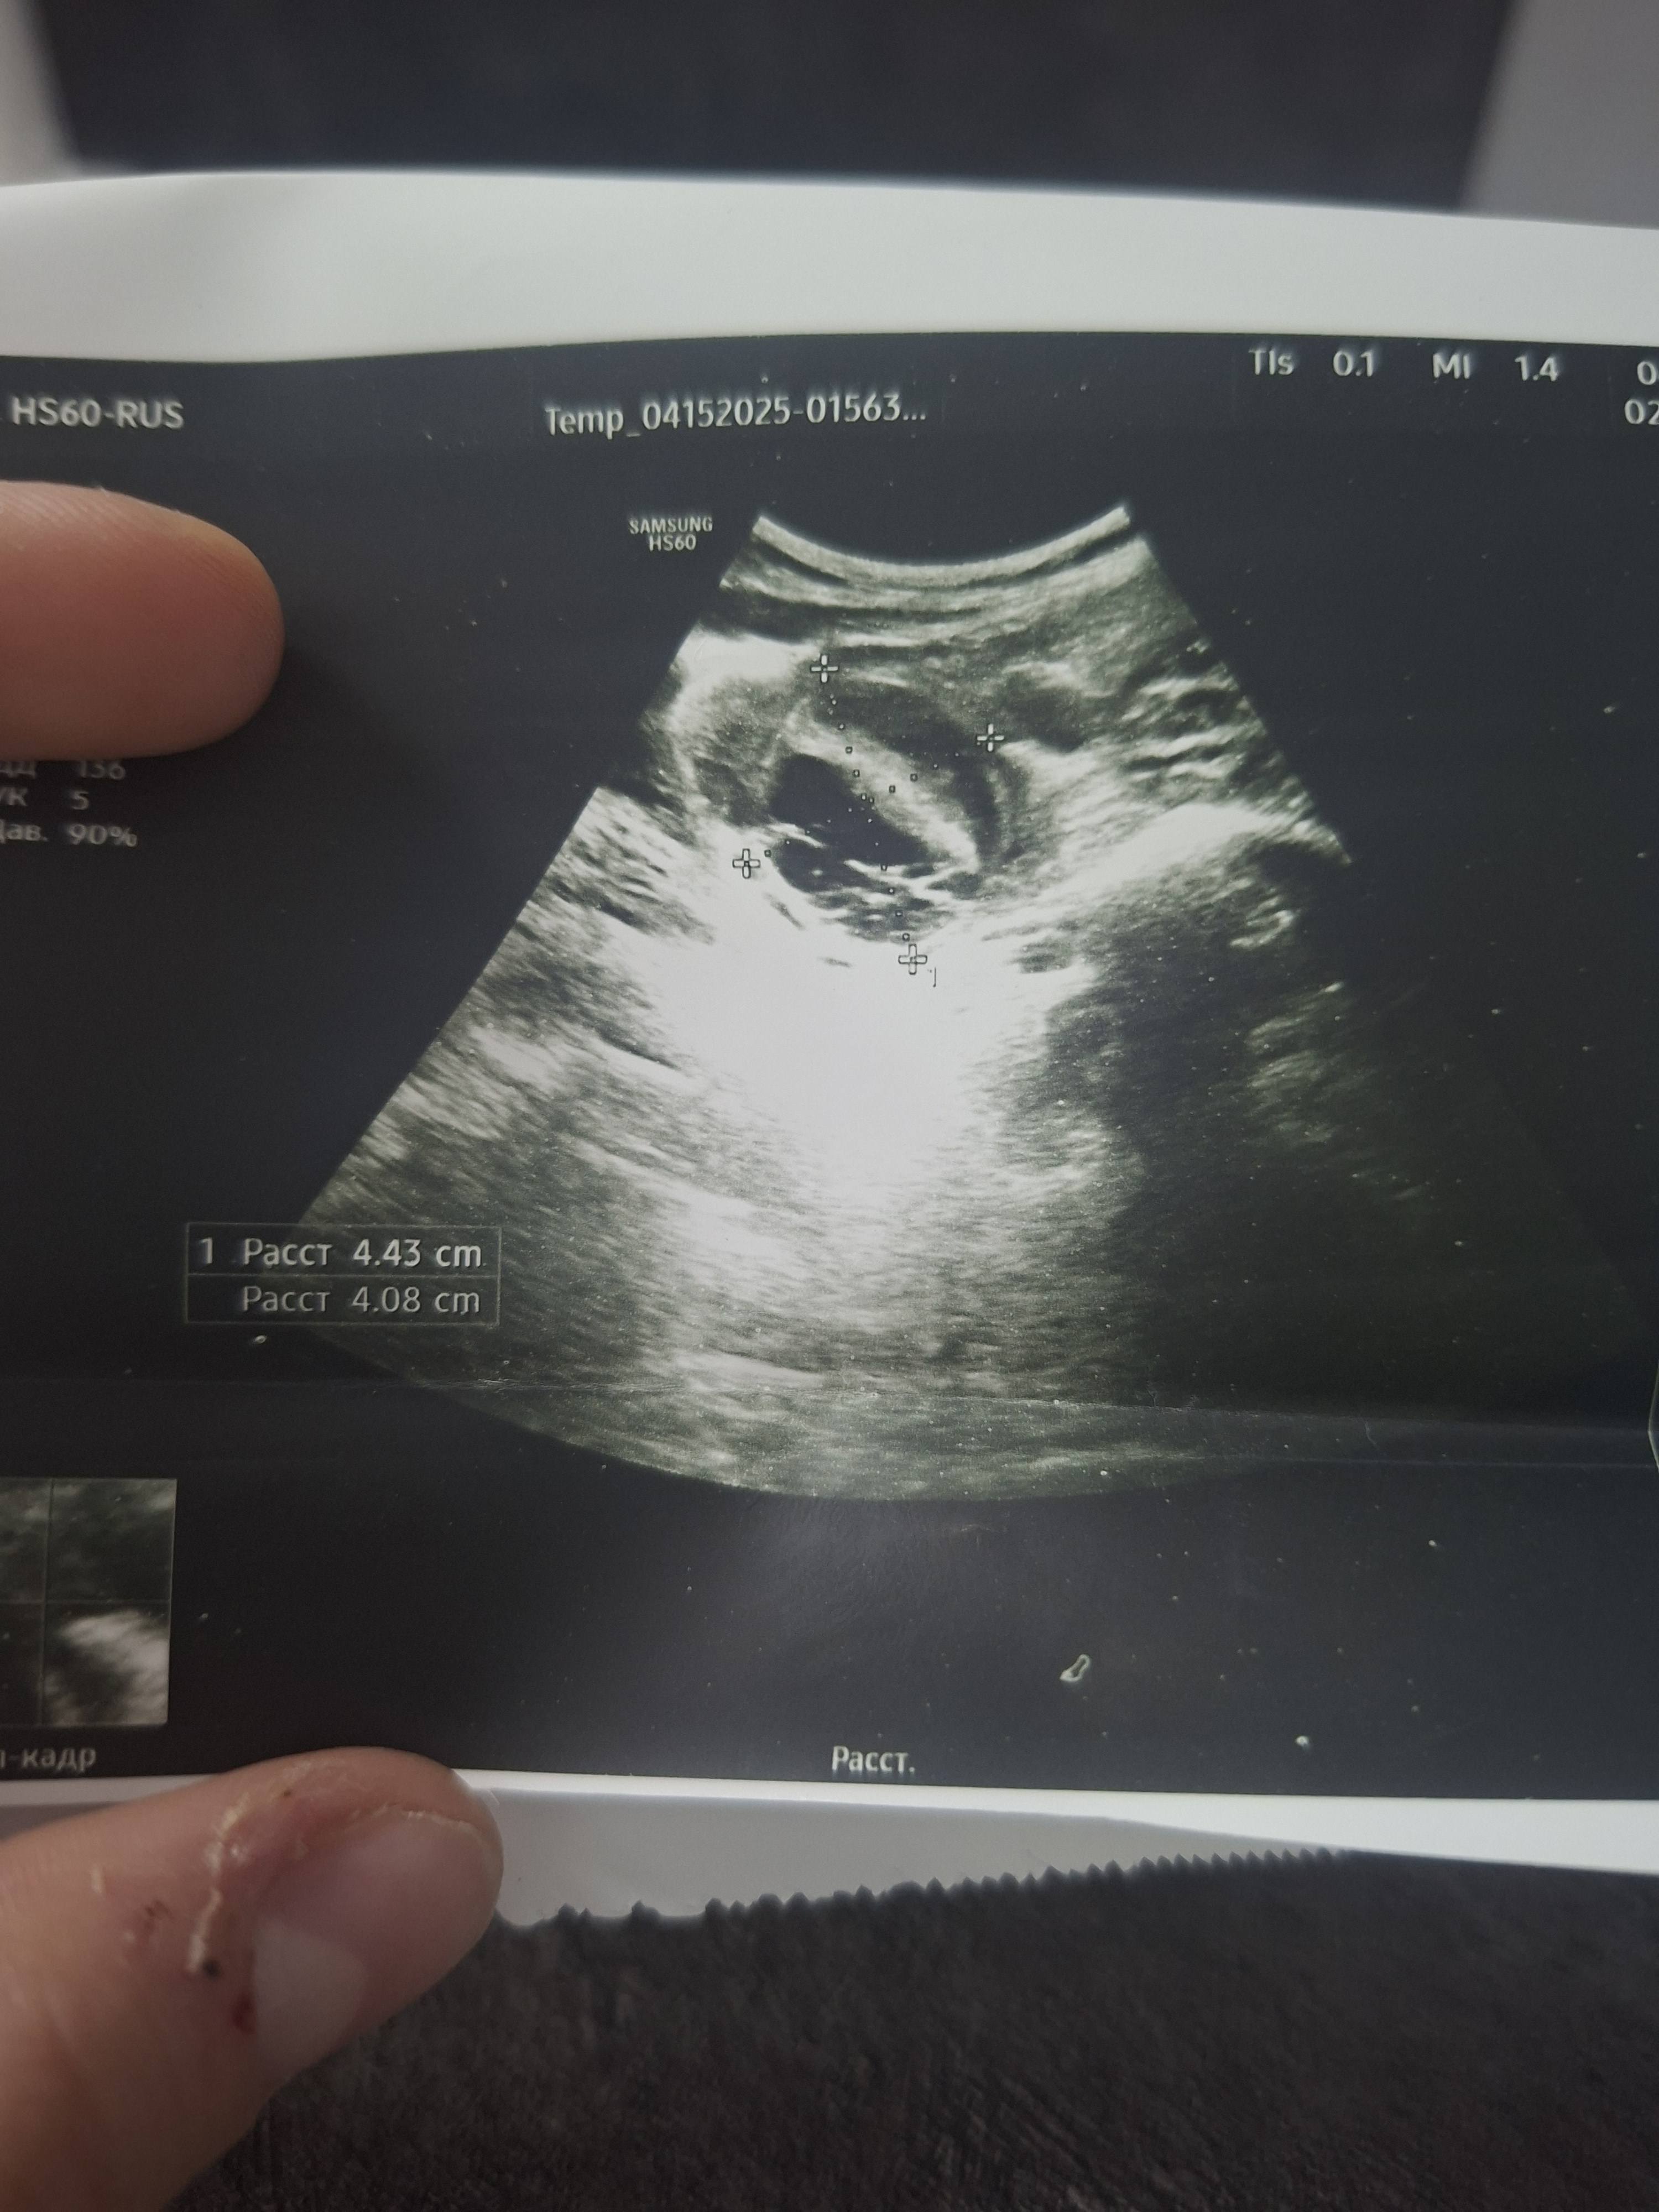

Здравствуйте всем кто читает этот текст,меня зовут Ира мне 18 лет,пол года назад мне поставили диагноз киста яичника,нужна срочная операция, брала кредит но этих денег хватило лишь на обследование и препараты,буду очень благодарна любой финансовой помощи